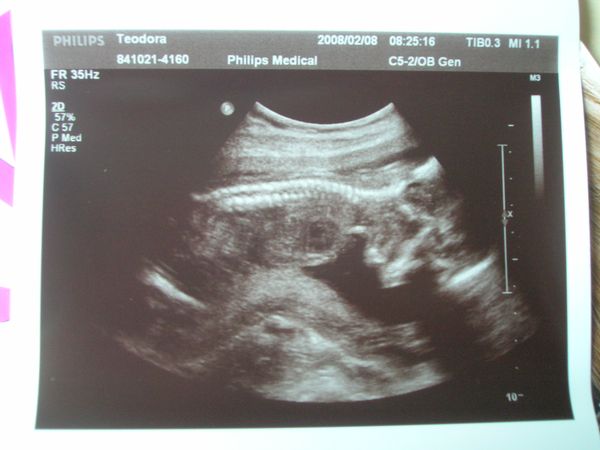

Én tegnap voltam 18 hetes genetikain ahol megerősítést kaptunk, hogy Dávidka Dávidka marad most már nincs mese

BPD:43mm THQ:39 mm ezeket mérték, az AFP értéke meg 1,21